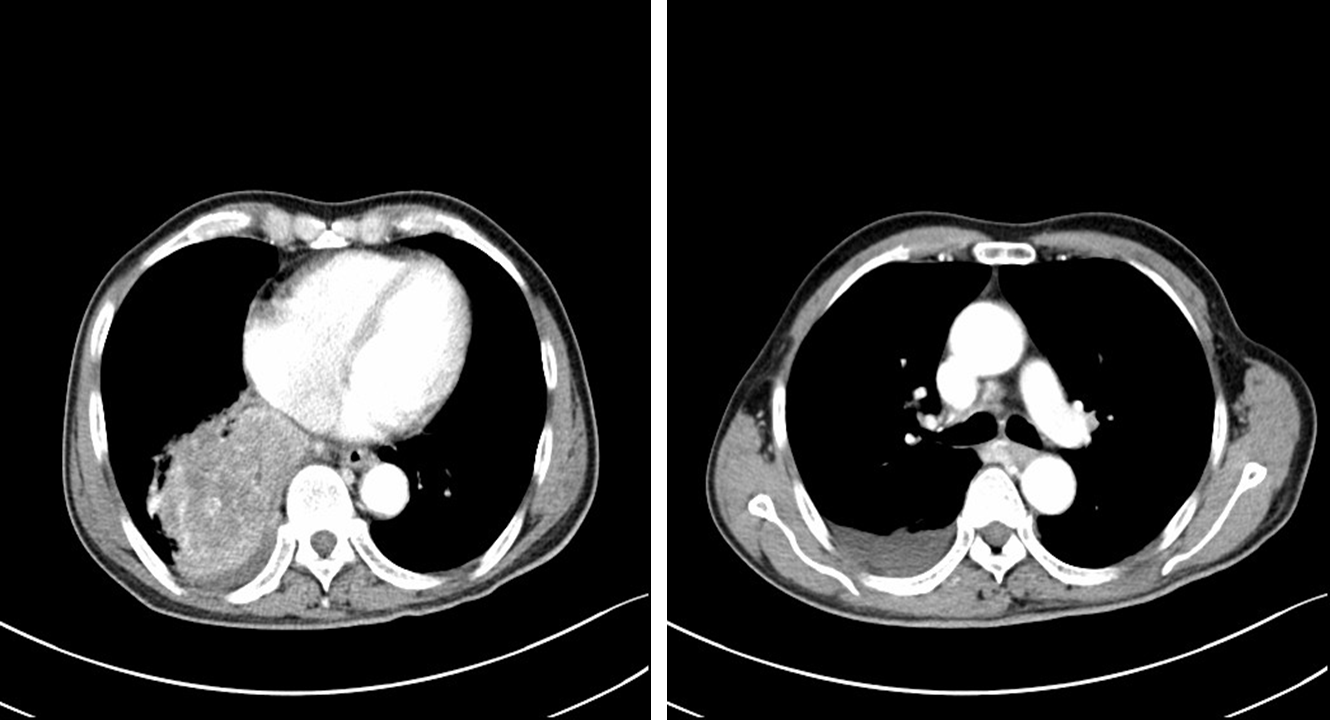

在沟通疗效和价格等因素后,患者自行选择信迪利单抗。2019年4月3日、4月30日、5月21日行信迪利单抗200mg D1治疗3个周期,患者症状缓解(自诉从“躺在床上”到“早上逛菜市场”)。2019年5月24日复查胸部CT示:右肺下叶软组织肿块影范围较前明显缩小,强化不均,范围约77mm *50mm。

图4. 2019年5月24日复查

2019年6月12日、7月2日继续行信迪利单抗200mg D1治疗2周期。2019年8月14日继续随访CT,结果示右肺下叶软组织肿块影范围较前明显缩小,强化不均,范围约28mm * 20mm,邻近胸膜增厚。疗效评价为部分缓解(PR),接近完全缓解(CR)。

图5. 2019年8月24日复查